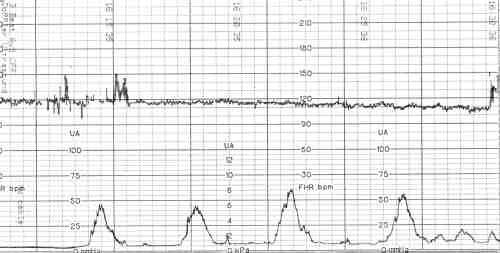

При анализе полученной кардиотокограммы плода оценивают следующие показатели:

• базальный ритм частоты сердцебиения плода, то есть среднее значение ЧСС между мгновенными показателями частоты сердечных сокращений либо в перерыве между схватками, либо за 10-минутный промежуток;

• базальные изменения – это колебания ЧСС плода, которые происходят независимо от сокращений матки;

• периодические изменения – это изменения ЧСС плода, которые происходят в ответ на сокращение матки;

• амплитуда – это  разница в значениях ЧСС между базальным ритмом и базальными и периодическими изменениями;

• время восстановления – отрезок времени, следующий за окончанием сокращения матки и возврату к базальному ритму ЧСС;

• акцелерации или возрастание ЧСС на 15-25 в минуту по отношению к базальному ритму (благоприятный признак, подтверждает удовлетворительное состояние плода, возникают в ответ на шевеление, тесты, схватку);

• децелерации – урежение ЧСС на 30 и больше и длящееся не менее 30 секунд.

Показатели нормальной антенатальной кардиотокограммы:

• базальный ритм составляет 120-160 в минуту;

• амплитуда вариабельности ритма в пределах 10-25 в минуту;

• децелерации отсутствуют;

• регистрация 2 и более акцелераций в течение 10 минут записи.